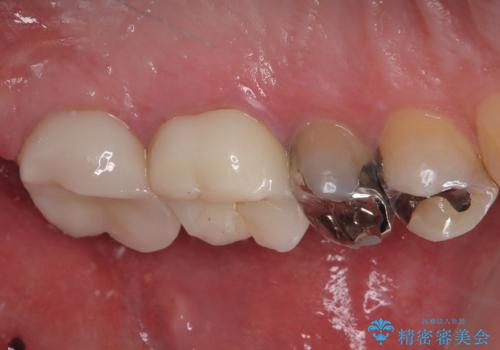

拡大鏡視野下でコンポジットレジン、虫歯を除去しオールセラミッククラウンに適した形に整えました。

歯と歯茎の間に圧排糸と言われる糸を入れてシリコーン印象材にて型どりをしました。

見た目、機能面共に満足していただけました。